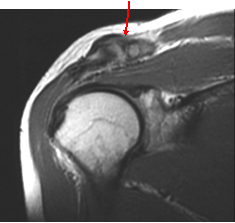

A-C Joint degenerative changes